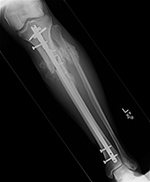

A short one-third tubular plate and screws plus interfragmentary screw stabilize a healing distal fibular fracture. An associated stress fracture (arrow) is in the distal tibial metaphysis from altered weight-bearing from the fibular fracture. |